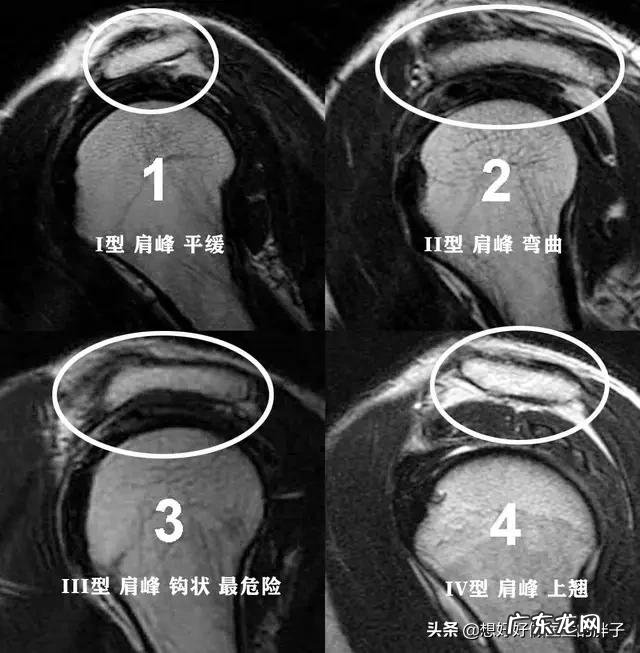

我们的肩关节的肩峰形态并不是所有人都一样的的,目前将肩关节的肩峰分为四型,一型是平缓的,二型是略微弯曲的,而三型是钩状的,四型是向上翘的,而这其中的三型肩峰由于是钩状的,会减少在肩关节活动时,肩峰与肱骨头之间的距离,会造成两者之间的撞击 。